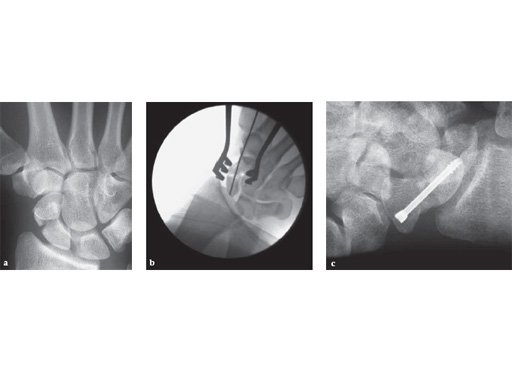

Acute scaphoid fracture treated percutaneously with the 3.0 mm HCS

a preop AP

b intraop AP

c 2 wks obl

Case provided by D Campbell, Leeds